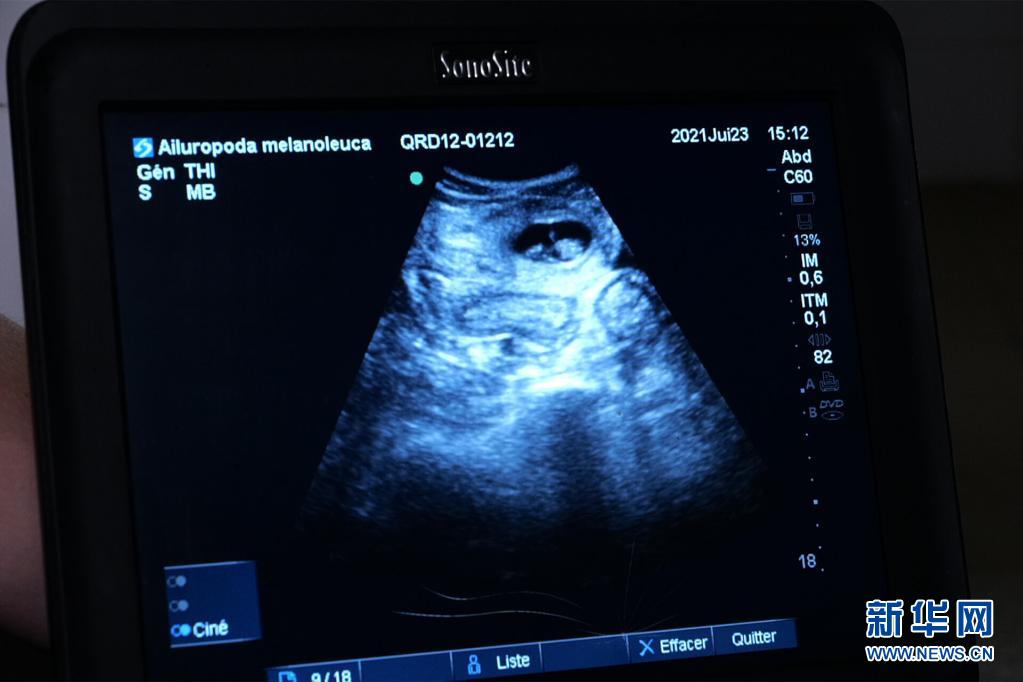

这是7月23日在法国中部圣艾尼昂市博瓦勒野生动物园拍摄的大熊猫“欢欢”的超声波检查照片。新华社发(博瓦勒野生动物园供图)

博瓦勒野生动物园当天发表新闻公报说,继20日发现“欢欢”腹中首个胚胎后,动物园兽医23日在为“欢欢”做超声波检查时,在其子宫另一侧发现第二个胚胎。